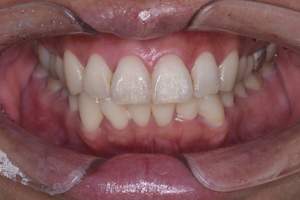

歯石除去

治療前

治療後

| 年齢 | 56歳・女性 |

| 主訴 | 主訴:歯石除去・検診 治療部位:全顎 |

| 治療内容 | 初診検査・歯石除去 |

| 治療期間 | 60分 |

| 費用 | 合計約5,000円 初診検査約3,000〜4,000円 歯石除去約1,000円 (2024年5月現在) (歯の本数や検査内容で料金が変動します。) |

| リスク・副作用 | ・歯ぐきの炎症がある場合は歯石除去中に出血を伴う可能性があります。 ・処置後に歯がしみることがあります。 ・歯ぐきの炎症が軽減すると歯ぐきが引き締まり、歯が長く見えることがあります。 |

| 治療方針 | ブラッシング指導・縁上歯石除去後に縁下歯石除去を行う |

| 特記事項 | 15年ぶりの歯科医院 |

| 担当者所見 | 歯ブラシは1日2回1分程度ですぐに終わらせていた。 歯科医院にも行かなくなり、舌でも感じる前歯の裏側の歯石が気になるとのことでした。 今回のクリーニングを機にセルフケアへのモチベーションが高まり、適切なブラッシング方法を学び実践したいと仰ってくださいました。 歯ブラシ習慣の見直しを相談し、動かし方の練習も一緒に行いました。 今後は縁下歯石(歯ぐきの中に付着する歯石)の除去を全顎的に行っていく予定です。 |